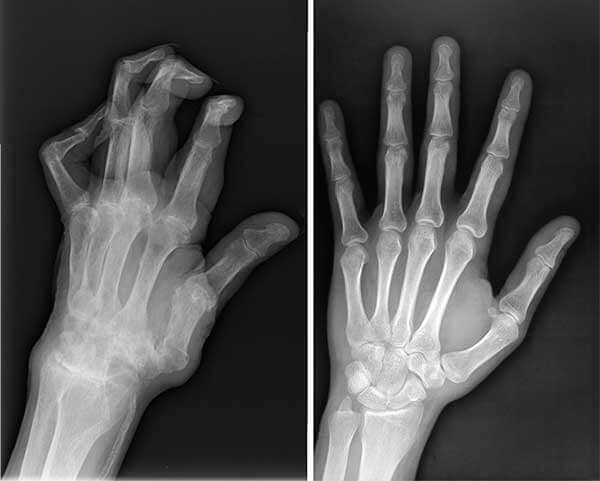

Pomogao je i mom suprugu, Milanu, koji ima artritis u šakama. Fenomenalno deluje čak i kod takvih upala!

Rendgenski snimci Milanovih šaka pre i posle Nautubone Gela.

Ruke mog supruga – sada je sve u redu.